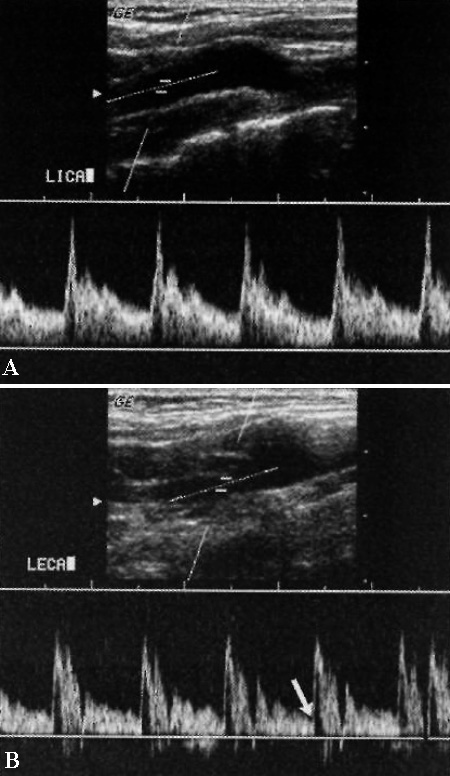

Сонные артерии характеризуются однонаправленным кровотоком на протяжение всего сердечного цикла. Внутренняя сонная артерия имеет гладкую форму и постоянный кровоток в систолу и в диастолу (это обусловлено низким сопротивлением внутри сосудов головного мозга): максимальная систолическая скорость составляет в среднем 0,6-1,0 м/с.

Кривая наружной сонной артерии демонстрирует острые пики в систолу и небольшую скорость в конце диастолы, что обусловлено высоким сосудистым сопротивлением ее ветвей. Допплерография общей сонной артерии демонстрирует сочетание признаков кровотока высокого и низкого сопротивления – острые пики в систолу и постоянный кровоток в диастолу (фото 3).

Фото 3. Допплерограмма нормальных сонных артерий. А – внутренняя сонная артерия: отмечается гладкая форма кривой – постоянный поток на протяжение всей систолы и диастолы. В – наружная сонная артерия: наблюдаются типичные пики в систолу, стрелкой обозначен момент снижения скорости кровотока ближе к концу диастолы.